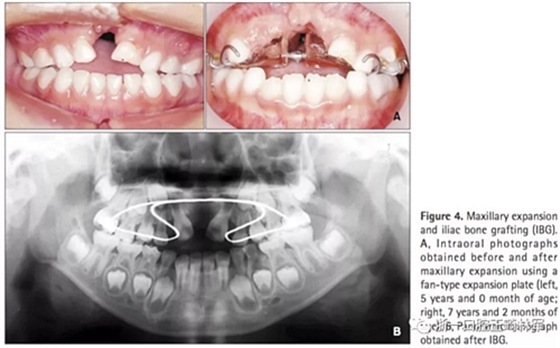

第一階段(圖4及表2)

上頜牙弓使用fan-type擴弓器(慢擴,0.25mm/周)。7歲7月時行IBG,隨后上頜恒側(cè)切牙與移植區(qū)萌出。